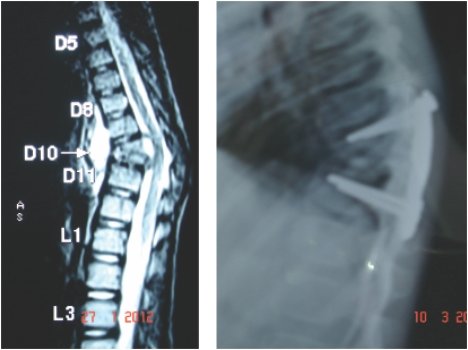

Double cord syndrome – DIASTOMATOMYELIA – is a very rare entity, wherein patient

is having congenital deformity of spine with separation of the spinal cord into

two halves by a bony or fibrous septum It is a great challenge to operate these

pts as , if something goes wrong, pt would become paraplegic for her life time.

Perticularly, in this case, as pt was only 9 years old and having congenital deformity

of the vertebrae, it was corrected simultaneously at Sola civil hospital - ahmedabad.